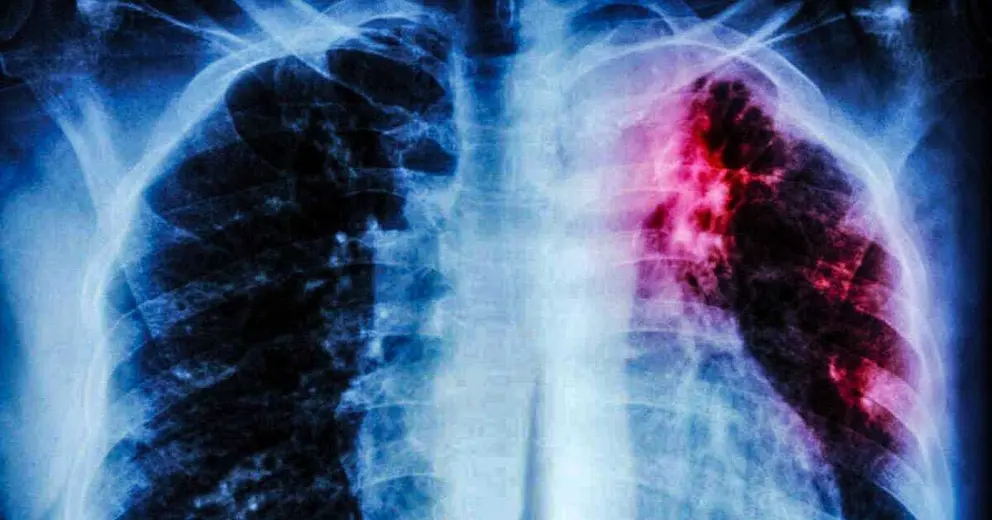

Un compuesto del té verde podría acabar con la tuberculosis

Un antioxidante encontrado en la planta de té verde podría convertirse en la clave para combatir la tuberculosis, según ha descubierto un equipo de científicos internacionales dirigido por la Universidad Tecnológica de Nanyang (Singapur) en un estudio publicado en 'Scientific Reports'.